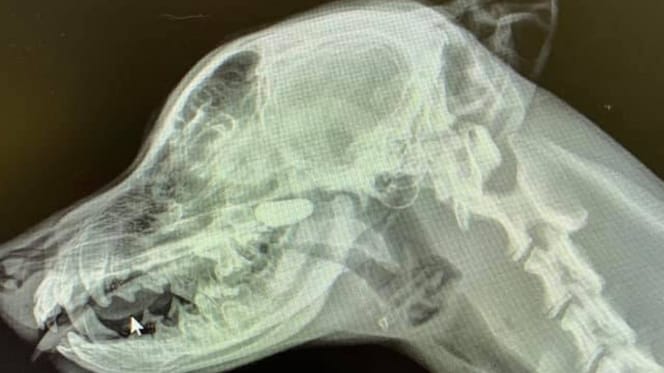

Röntgenfoto van Labrador pup onthult bizarre ontdekking in neus

De dierenarts zet haar onderzoek voort en besluit röntgenfoto's van de jonge hond te maken. Eerst van de borstkas, maar hoe goed Sarah ook kijkt, ze ziet niets verdachts op de foto. Ze vraagt vervolgens om een profielfoto van de kop en nek. En deze keer is het raak!

In de neusholtes is duidelijk een vreemd voorwerp te zien dat daar absoluut niet thuishoort. Het blijkt een steentje te zijn dat de pup in zijn neus heeft weten te krijgen. Zodra het voorwerp was verwijderd, voelde de kleine Labrador zich meteen stukken beter.